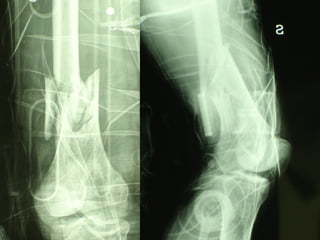

INDICAZIONI COMUNI Fratture sovracondiloidee Fratture intercondiliodee Fratture diafisarie distali PARTICOLARI Fratture con grave osteoporosi Fratture periprotesiche

VANTAGGI CHIRURGIA MININVASIVA Mini Open Inserimento della placca sottocutaneo per scivolamento Viti percutanee Preservazione dei tessuti molli Ridotto danno vascolare Rapida ripresa funzionale

F, 68 y

LISS  NCB

NCB